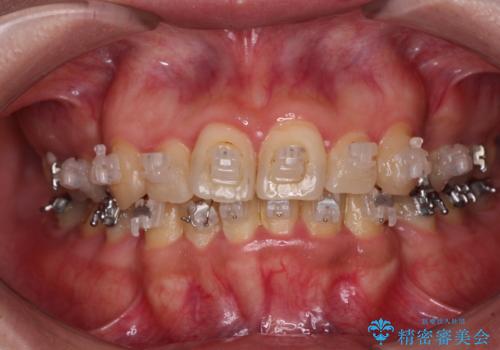

- 海外で抜歯矯正を開始し、治療途中で帰国したため、転院先を探しているとのことで来院された患者様です。

ワイヤーは抜けてしまい、後戻りが始まっている状態でしたが、既存の装置を継続利用して受け入れてくれる医院が見つからないとのことでした。

当院では、張り替える必要のある部位は張り替えることで継続することとし、抜歯スペースを閉じていくように治療を行うこととしました。